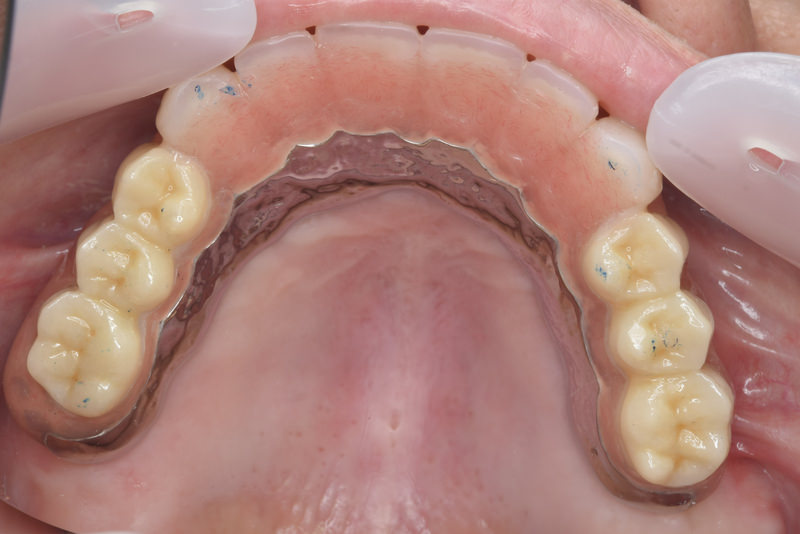

症例2【70代女性】主訴 義歯がわずらわしい・しっかり噛みたい

治療前

治療後(2年経過)

※説明

主訴 上顎のみ部分義歯を使用しているが、入れ歯が煩わしい、固定制のインプラントにして欲しいと来院。

左右上顎第一大臼歯相当は、骨の高さが不足しており、ソケットリフト(骨造成)の必要があり、左右第一小臼歯、第一大臼歯支台のインプラントブリッジを提案。

採血で得られた、CGFメンブレンとAFGブロック(人工骨β‐TCPとAFGを混ぜたブロック)を使用し骨を挙上し、インプラントを埋入。

右下のブリッジも、短根歯で動揺が激しい為に抜歯し、インプラント埋入。

上顎の免荷期間は約4ヶ月、下顎の免荷期間は約2ヶ月を経て、仮歯を装着、リハビリをし、メタルボンド(金属焼付ポーセレン)を装着。

費用 280万(オペ・ソケットリフト・人工骨・採血による濃縮血小板生成・仮歯・最終補綴物まで含む)